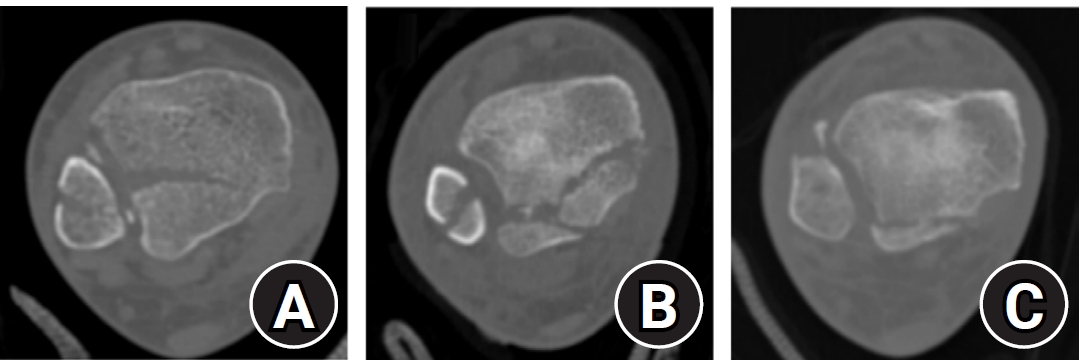

Demographic and clinical data were obtained from electronic medical records. Radiographic data were derived from 3D-CT scans. Radiographic analysis was performed using 3D-CT to assess the characteristics of both lateral and posterior malleolar fractures. Lateral malleolar fracture patterns were determined by measuring the vertical distance between the highest posterior cortex or lowest anterior cortex of the fracture and a line perpendicular to the tibial axis at the distal tibial articular surface. The angle between the posterior cortex of the lateral malleolus and the line connecting the anterior and posterior cortical points was defined as the fracture angle (Fig. 1).

Radiographic assessment of fracture characteristics. (A) Posterior height (a) and anterior height (b) represent the vertical distances from the highest point of the posterior cortex (▼) and the lowest point of the anterior cortex (▲) of the distal lateral fibula, respectively, to the line perpendicular to the tibial axis that intersects the distal tibial articular plafond. (B) The fracture angle (c) of the lateral malleolar fragment is defined as the angle between the posterior cortex of the lateral malleolus and the line connecting the anterior and posterior cortical points of the fracture.

Fig. 1. Radiographic assessment of fracture characteristics. (A) Posterior height (a) and anterior height (b) represent the vertical distances from the highest point of the posterior cortex (▼) and the lowest point of the anterior cortex (▲) of the distal lateral fibula, respectively, to the line perpendicular to the tibial axis that intersects the distal tibial articular plafond. (B) The fracture angle (c) of the lateral malleolar fragment is defined as the angle between the posterior cortex of the lateral malleolus and the line connecting the anterior and posterior cortical points of the fracture.